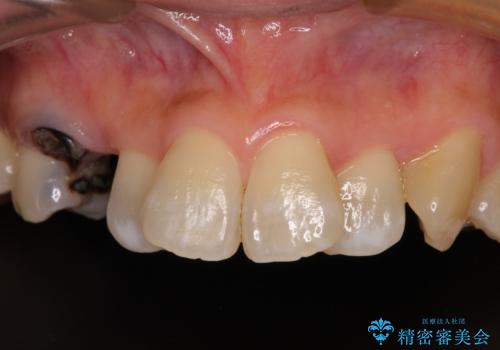

- 前歯などに、むし歯でボロボロになった歯があるとのことで来院された患者様です。

むし歯により歯冠が崩壊してから長いこと経過しているとのことで、歯を失ったことによる他の歯への影響はあまりないと判断されたため、審美領域である上顎前歯部のみにインプラント補綴治療を行うこととしました。

2本の歯が前後に重なった状態でむし歯となっていたので、抜歯後に歯肉や骨の状態が落ち着くのを待ち、インプラントを埋入することとしました。